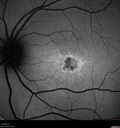

Stargardt Disease - Very Mild - 24 year old157 viewsThis patient has 3 different ABCA4 mutations. His mother and sister have stargardts and his father has RP. His sisters images are also on Retinagallery.com